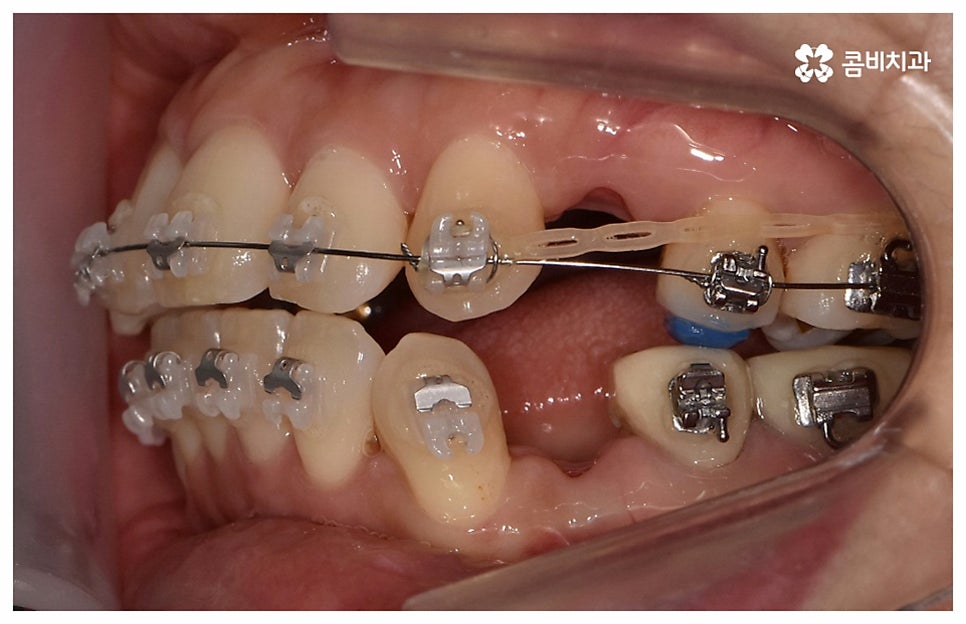

검진 후 부분 교정이 가능하지 않은 케이스라고 해도 요즘은 심미적인 교정 장치가 많이 나와 있으며 장치 자체로 인해 결과에 미치는 영향이 크지 않기 때문에 자신의 상황에 맞는 장치를 직접 선택할 수 있으니 의료진과 충분히 상담을 해 보시면 도움 받아 보실 수 있을 거예요. 특히 치아 색상의 브라켓을 이용한 세라믹 장치들이 심미성이 뛰어난데, 그 중에서도 자가결찰방식을 이용한 클리피씨 교정 장치를 이용하면 눈에 크게 띄지 않을 뿐 아니라 보다 적은 힘으로 부드럽고 지속적인 치아 이동을 가능하게 하기 때문에 통증도 줄이고 전체 교정 기간 역시 단축시킬 수 있다는 장점이 있으니 이에 대해서도 자세하게 알아보시길 바라고 있습니다.

교정의 경우 보통 1년 반에서 2년 정도로 짧지 않은 기간이 걸리기 때문에 장치가 겉으로 드러나는 것에 대해 부담을 느끼시는 중장년분들이 많이 있습니다. 하지만 환자분들의 상황에 따라 부정 교합 정도가 심각하지 않고 골격적인 원인이 크지 않다면 6~8개월 정도 소요되는 부분 교정으로 필요한 부위만 보다 빠르고 간편하게 바로잡을 수 있으니 먼저 검진부터 진행해 보시길 권유드리고 있어요.

나이가 들어가면서 치아와 주위 조직들이 약해질 수 있고 치주 질환이 발생할 위험도 높아지기 때문에 중년치아교정 치료시 환자분들의 상황에 따른 맞춤 진료를 더욱 세심하게 진행할 필요가 있어요. 교정 방법이나 주의점에 대해서 꼼꼼하게 확인하고 계획을 세워야 할 뿐 아니라 교정 치료 전에 충치나 잇몸병과 같은 구강 질환이 발견되었다면 이를 미리 깨끗하게 치료하고 진행 과정 중간에도 장치에 음식물 찌꺼기가 끼지 않도록 위생 관리를 철저하게 해주며 치료 후 치아와 잇몸이 약해지지 않도록 환자분들 각각의 치아 이동 속도에 따라 무리하지 않는 것이 중요한 포인트라고 할 수 있습니다.